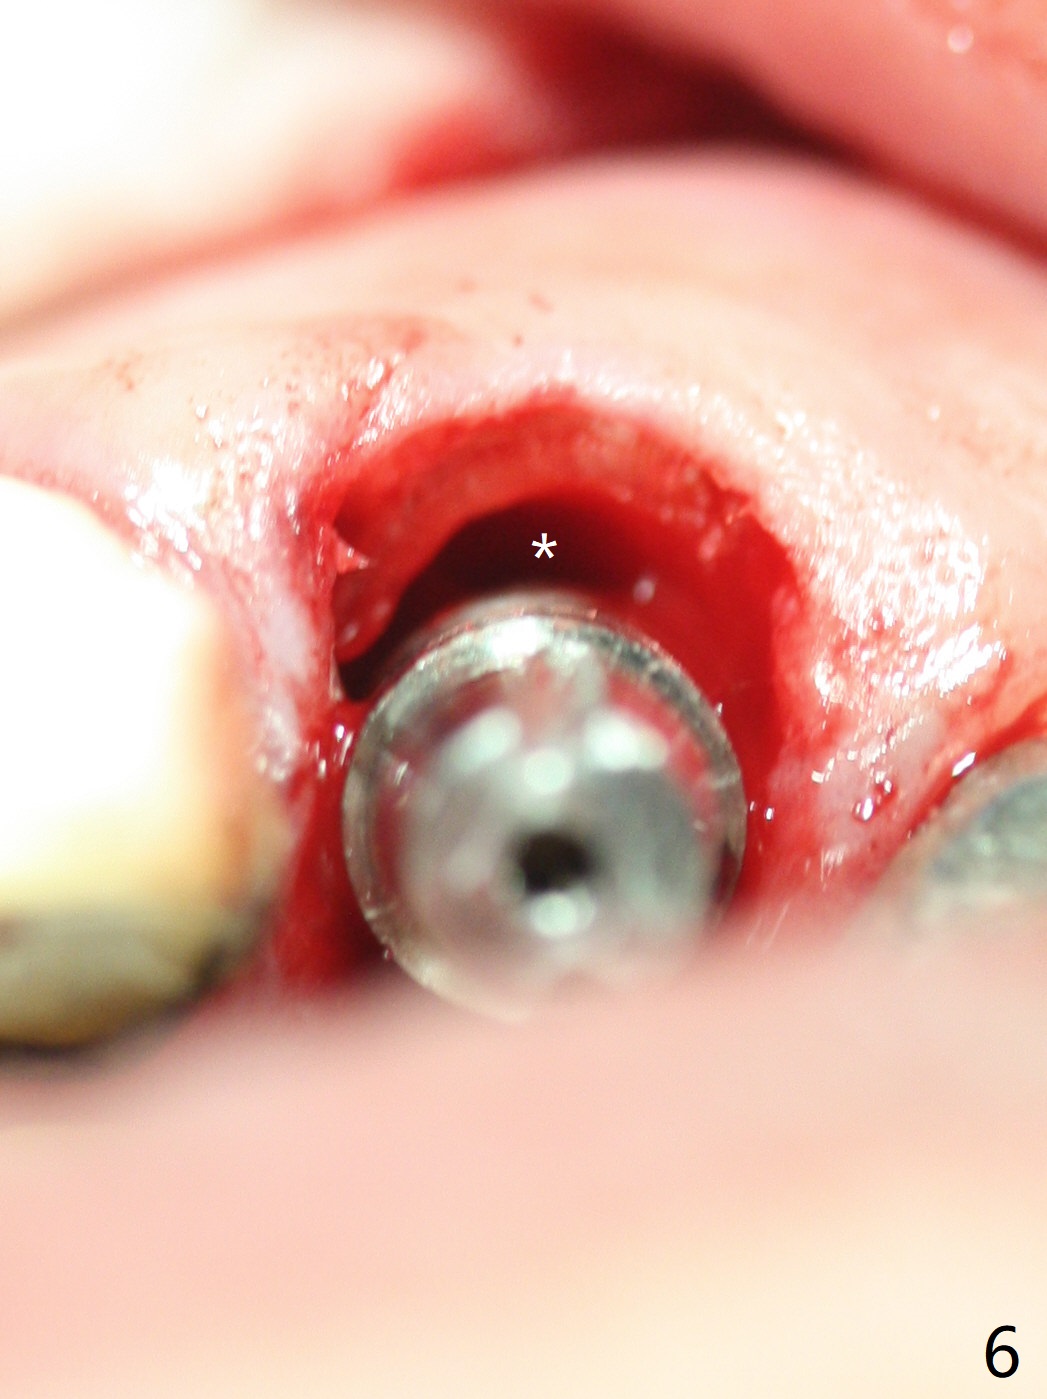

Extraction of the residual root at #11 (Fig.1) turns out to be difficult (Fig.2 (arrow: after use of small elevator). The tooth is sectioned (Fig.2 *); the palatal portion is removed, while the buccal one is trimmed until new moon-shaped and subgingival (Fig.3 * (gauze (G) packed in the socket while photo taking)). Initial osteotomy is 20 mm deep with nasal floor perforation (Fig.4). The subsequent depth is 17 mm (Fig.5). When a 5x17 mm tissue-level implant is placed (Fig.6,7; >60 Ncm), there is a gap between it and the socket shield (Fig.6 *). Gap-filling Vera Graft (Fig.8 *) also covers the shield prior to fabrication of an immediate provisional (Fig.9). There is no apparent bone loss 3.5 months postop (Fig.10). There is no buccal plate resorption 9 months postop (Fig.11). The implant is doing well 2 years postop (1 year 9 months post cementation, Fig.12).